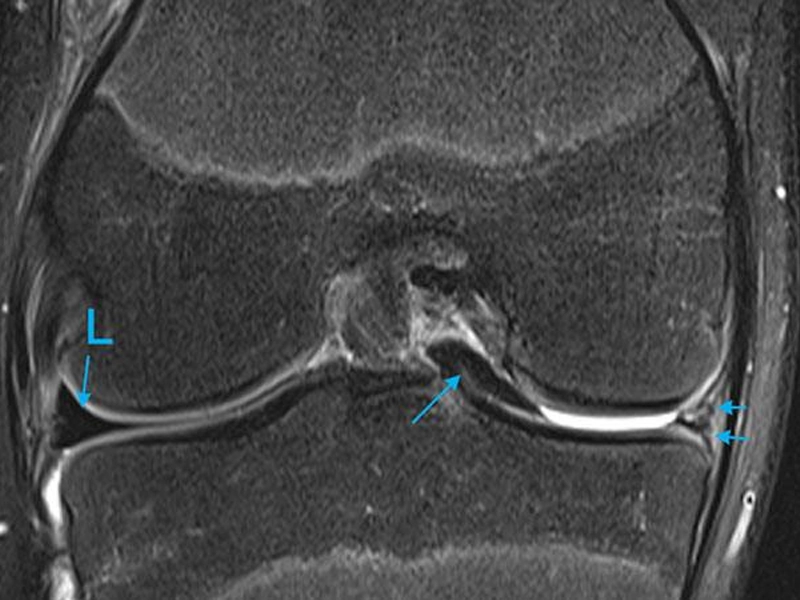

عکس mri پارگی مینیسک زانو

در بسیاری موارد، معاینه فیزیکی توسط پزشک می‌تواند پارگی مینیسک را مطرح کند، اما برای تأیید تشخیص، تعیین محل دقیق پارگی و نوع آن، تصویر MRI (تصویربرداری تشدید مغناطیسی) بهترین و دقیق‌ترین روش محسوب می‌شود. برخلاف رادیوگرافی معمولی که فقط استخوان‌ها را نشان می‌دهد، MRI توانایی نمایش کامل بافت‌های نرم از جمله مینیسک، رباط‌ها و […]